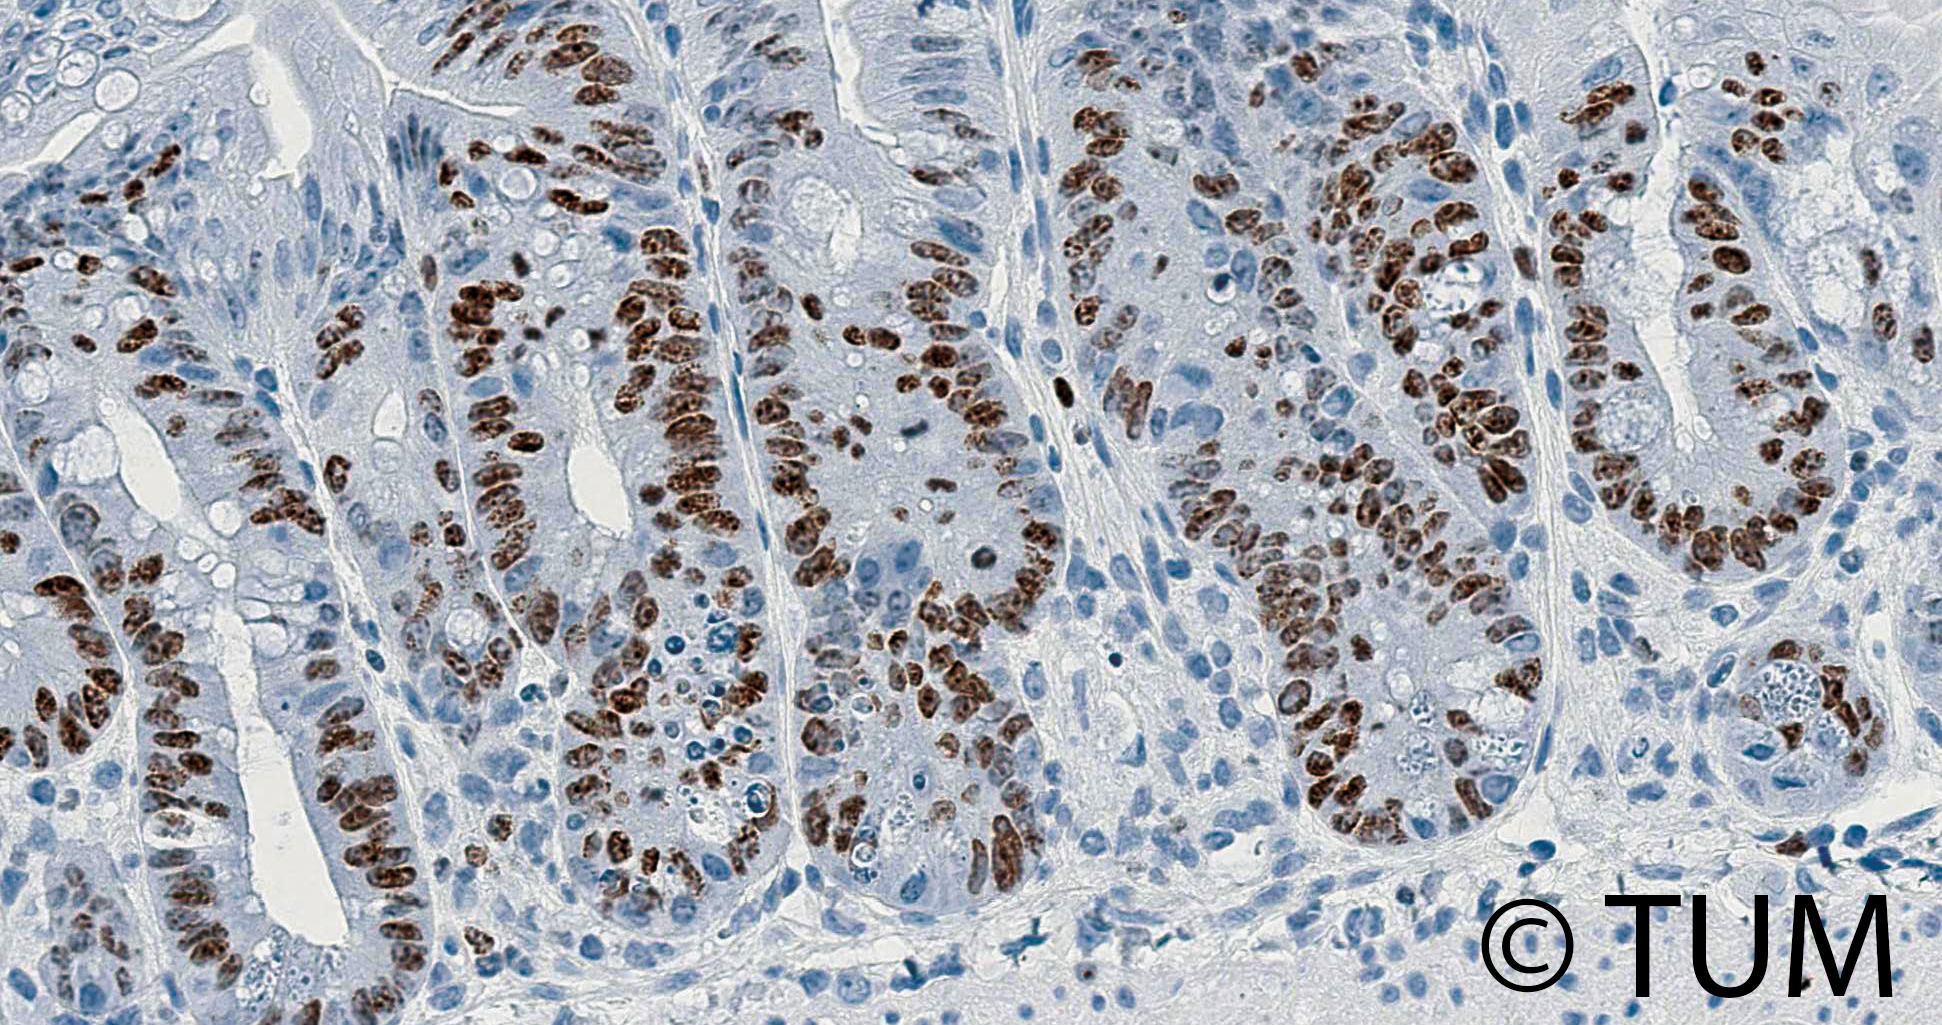

Abb. 1 Proliferierende Epithelzellen (braun markiert) im Darm eine Woche nach einer Bestrahlung des Bauchraums.

Ursächlich sind neben einer direkten zytotoxischen Wirkung auf Epithel- und Stromazellen auch indirekte immunologische Mechanismen. Die gastrointestinale Toxizität ist deshalb ein dosislimitierender Faktor von Krebstherapien, weshalb Forschende der Klinik und Poliklinik für RadioOnkologie und Strahlentherapie der TU München nach einem Weg suchen, das Darmepithel zu regenerieren. Im Fokus ihrer Forschung stehen regulatorische T-Zellen (Treg): Diese unterstützen neben ihren immunsuppressiven Funktionen auch die Reparatur des Darmgewebes. Denn sowohl im Mausmodell als auch in Patientenproben konnten die Forschenden nachweisen, dass Treg die Entzündungssignale Interferon-gamma (IFNγ) und Interleukin-10 (IL-10) abgeben. Diese fördern gemeinschaftlich intestinale Stammzellen, die sowohl zu einer Heilung als auch zu einer langfristigen Regeneration des Darms nach immun- und strahlungsbedingten Schäden führen [Fischer JC et al. Signal Transduct Target Ther. 2025;10(1):384]. Das Forschungsteam arbeitet nun daran, neue therapeutische Ansätze zur Förderung der Darmreparatur zu entwickeln.